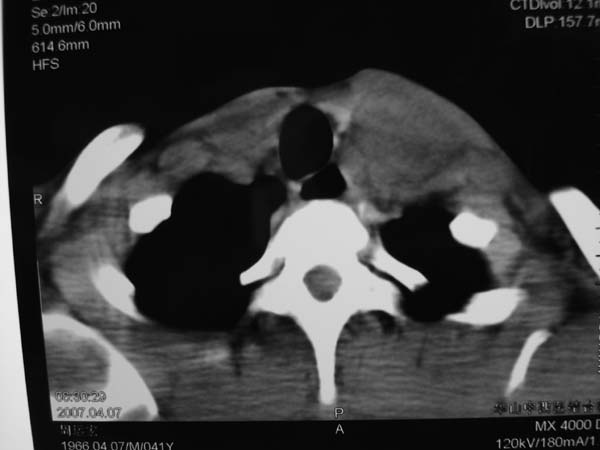

标题: CT7516[颌面颈部]:颈部病变,请会诊!

患者男性,37岁,农民,自觉左颈部肿大三天,无其它不适。

同甲状腺间有脂肪间隙存在,考虑不是来源于甲状腺,肿大淋巴结?

病灶边界较清,密度不均,其内可见坏死灶,左侧甲状腺受压,考虑神经源性肿瘤可能性大,建议穿刺活检。

病程短,症状轻,颈内动静脉显示不清,考虑血管病变。建议增强扫描。贸然穿刺可能会引起出血。